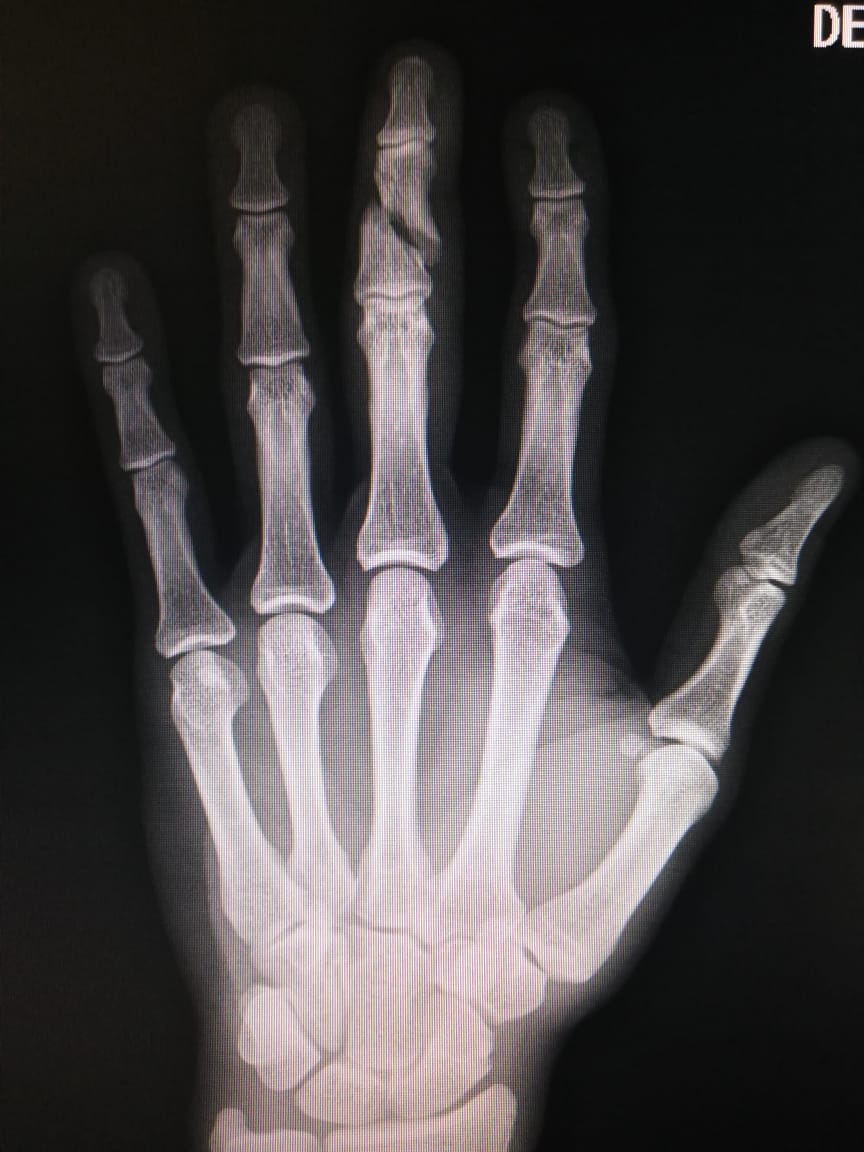

En uno de los entrenamientos el mediocampista antioqueño Michael López presentó una lesión en su mano y tuvo que ser intervenido quirúrgicamente, al cierre de esta edición se estaba realizando el procedimiento, “fue operado ayer en la tarde, luego tendremos el parte, las indicaciones del cirujano, fue una fractura de la segunda falange del dedo medio de la mano, solo esperamos la evolución de la cirugía” explicó Wilches.

Radiografía de la fractura en segunda falange del tercer dedo de una de las manos de Michael López

Diario del Huila consultó por la salud general del plantel y el galeno dijo, “el grupo principal que estuvo en el partido, estuvo de descanso, en general la mayoría se encuentra bien, un poco de cansancio pero manejable, sin embargo el martes sabremos más exactamente como estemos, todos descansaron el lunes, en el caso de los tres jugadores porque fueron específicos los cuales tuvimos que intervenir el caso de Andrés Amaya la radiografía fue el lunes en horas de la mañana, el caso de Michael López la fractura fue durante un entrenamiento en Neiva no estaba en el partido, y lo de Cardoza que es una herida que es de cuidado, el martes miraremos la evolución y sabremos con más precisión sobre el asunto”.